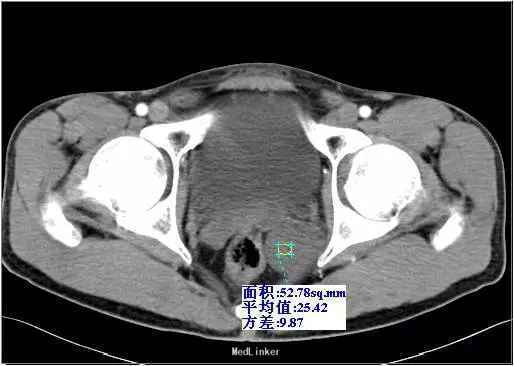

查体:左侧精囊区肿块,大小约3cm,质硬,活动度可,轻挤压痛,余体检无异常。实验室检查:血常规、生化、凝血、尿常规及肿瘤标记物化验未发现特殊异常。 影像检查:超声示盆腔内直肠中段左侧见一肿块图像,大小约4.4 cm×5.0 cm×3.2 cm,形状呈椭圆形,边界欠规整,内部为低回声,分布不均,后方回声无变化,彩色多普勒显示肿块内部可见少许点状血流信号。 CT示左侧精囊区见一肿块,大小约4.3 cm×3.6 cm;平扫呈稍低密度(相对邻近肌肉密度),密度不均,其内可见散在分布更低密度区,CT值约18-28HU,动脉期CT值20-28HU,静脉期CT值20-30HU,肿块边缘规整、边界清楚,与直肠膀胱分解清楚。